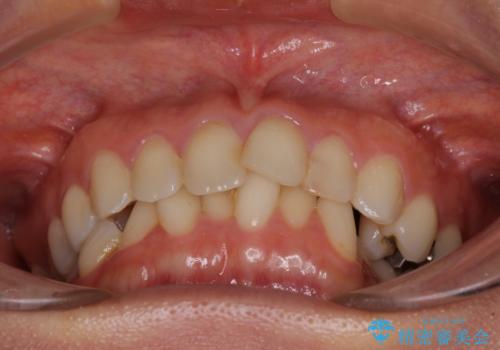

- 前歯のデコボコを気にして来院された患者様です。

IPR(歯と歯の間を削る)によってデコボコが解消するように設計し、インビザラインにより治療を行うこととしました。

下顎善の叢生をもう少し改善したかったのですが、患者様は十分に整ったとのことで治療を終えることになりました。